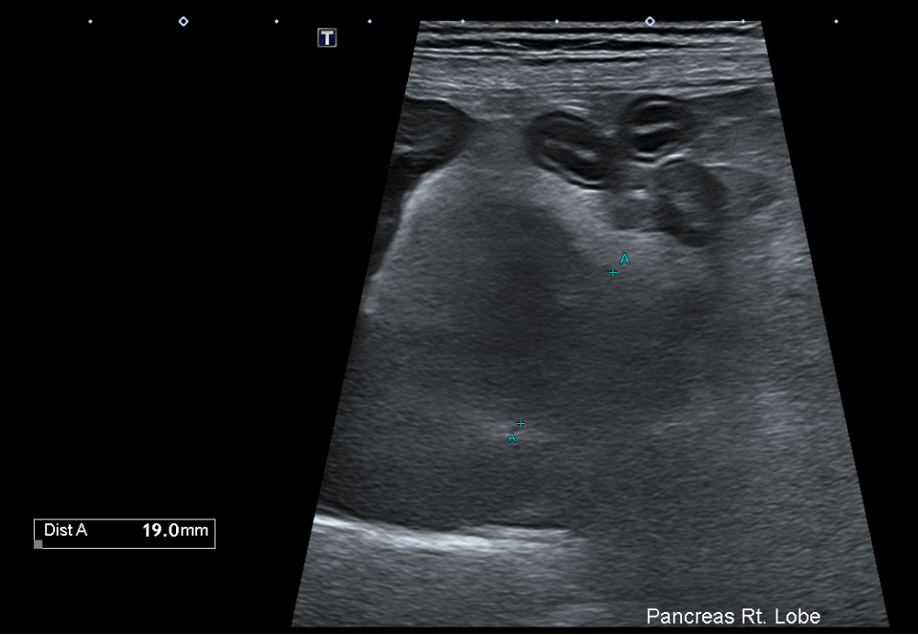

복부초음파

또한 복부 초음파상에서 뚜렷한 췌장 비후, 저에코성 음영, 주변 복막의 고에코성 소견 -> 확인되어 췌장염이 강력 의심되는 상황이었습니다.

Figure 2. 췌장 비후와 주변 복수 확인됨.

환자의 경우 뚜렷한 소화기 증상, 뚜렷한 염증 소견과 QPL 수치 상승, 복부초음파상 췌장염 비후, 복수 소견 확인되어 췌장염으로 진단되었습니다.